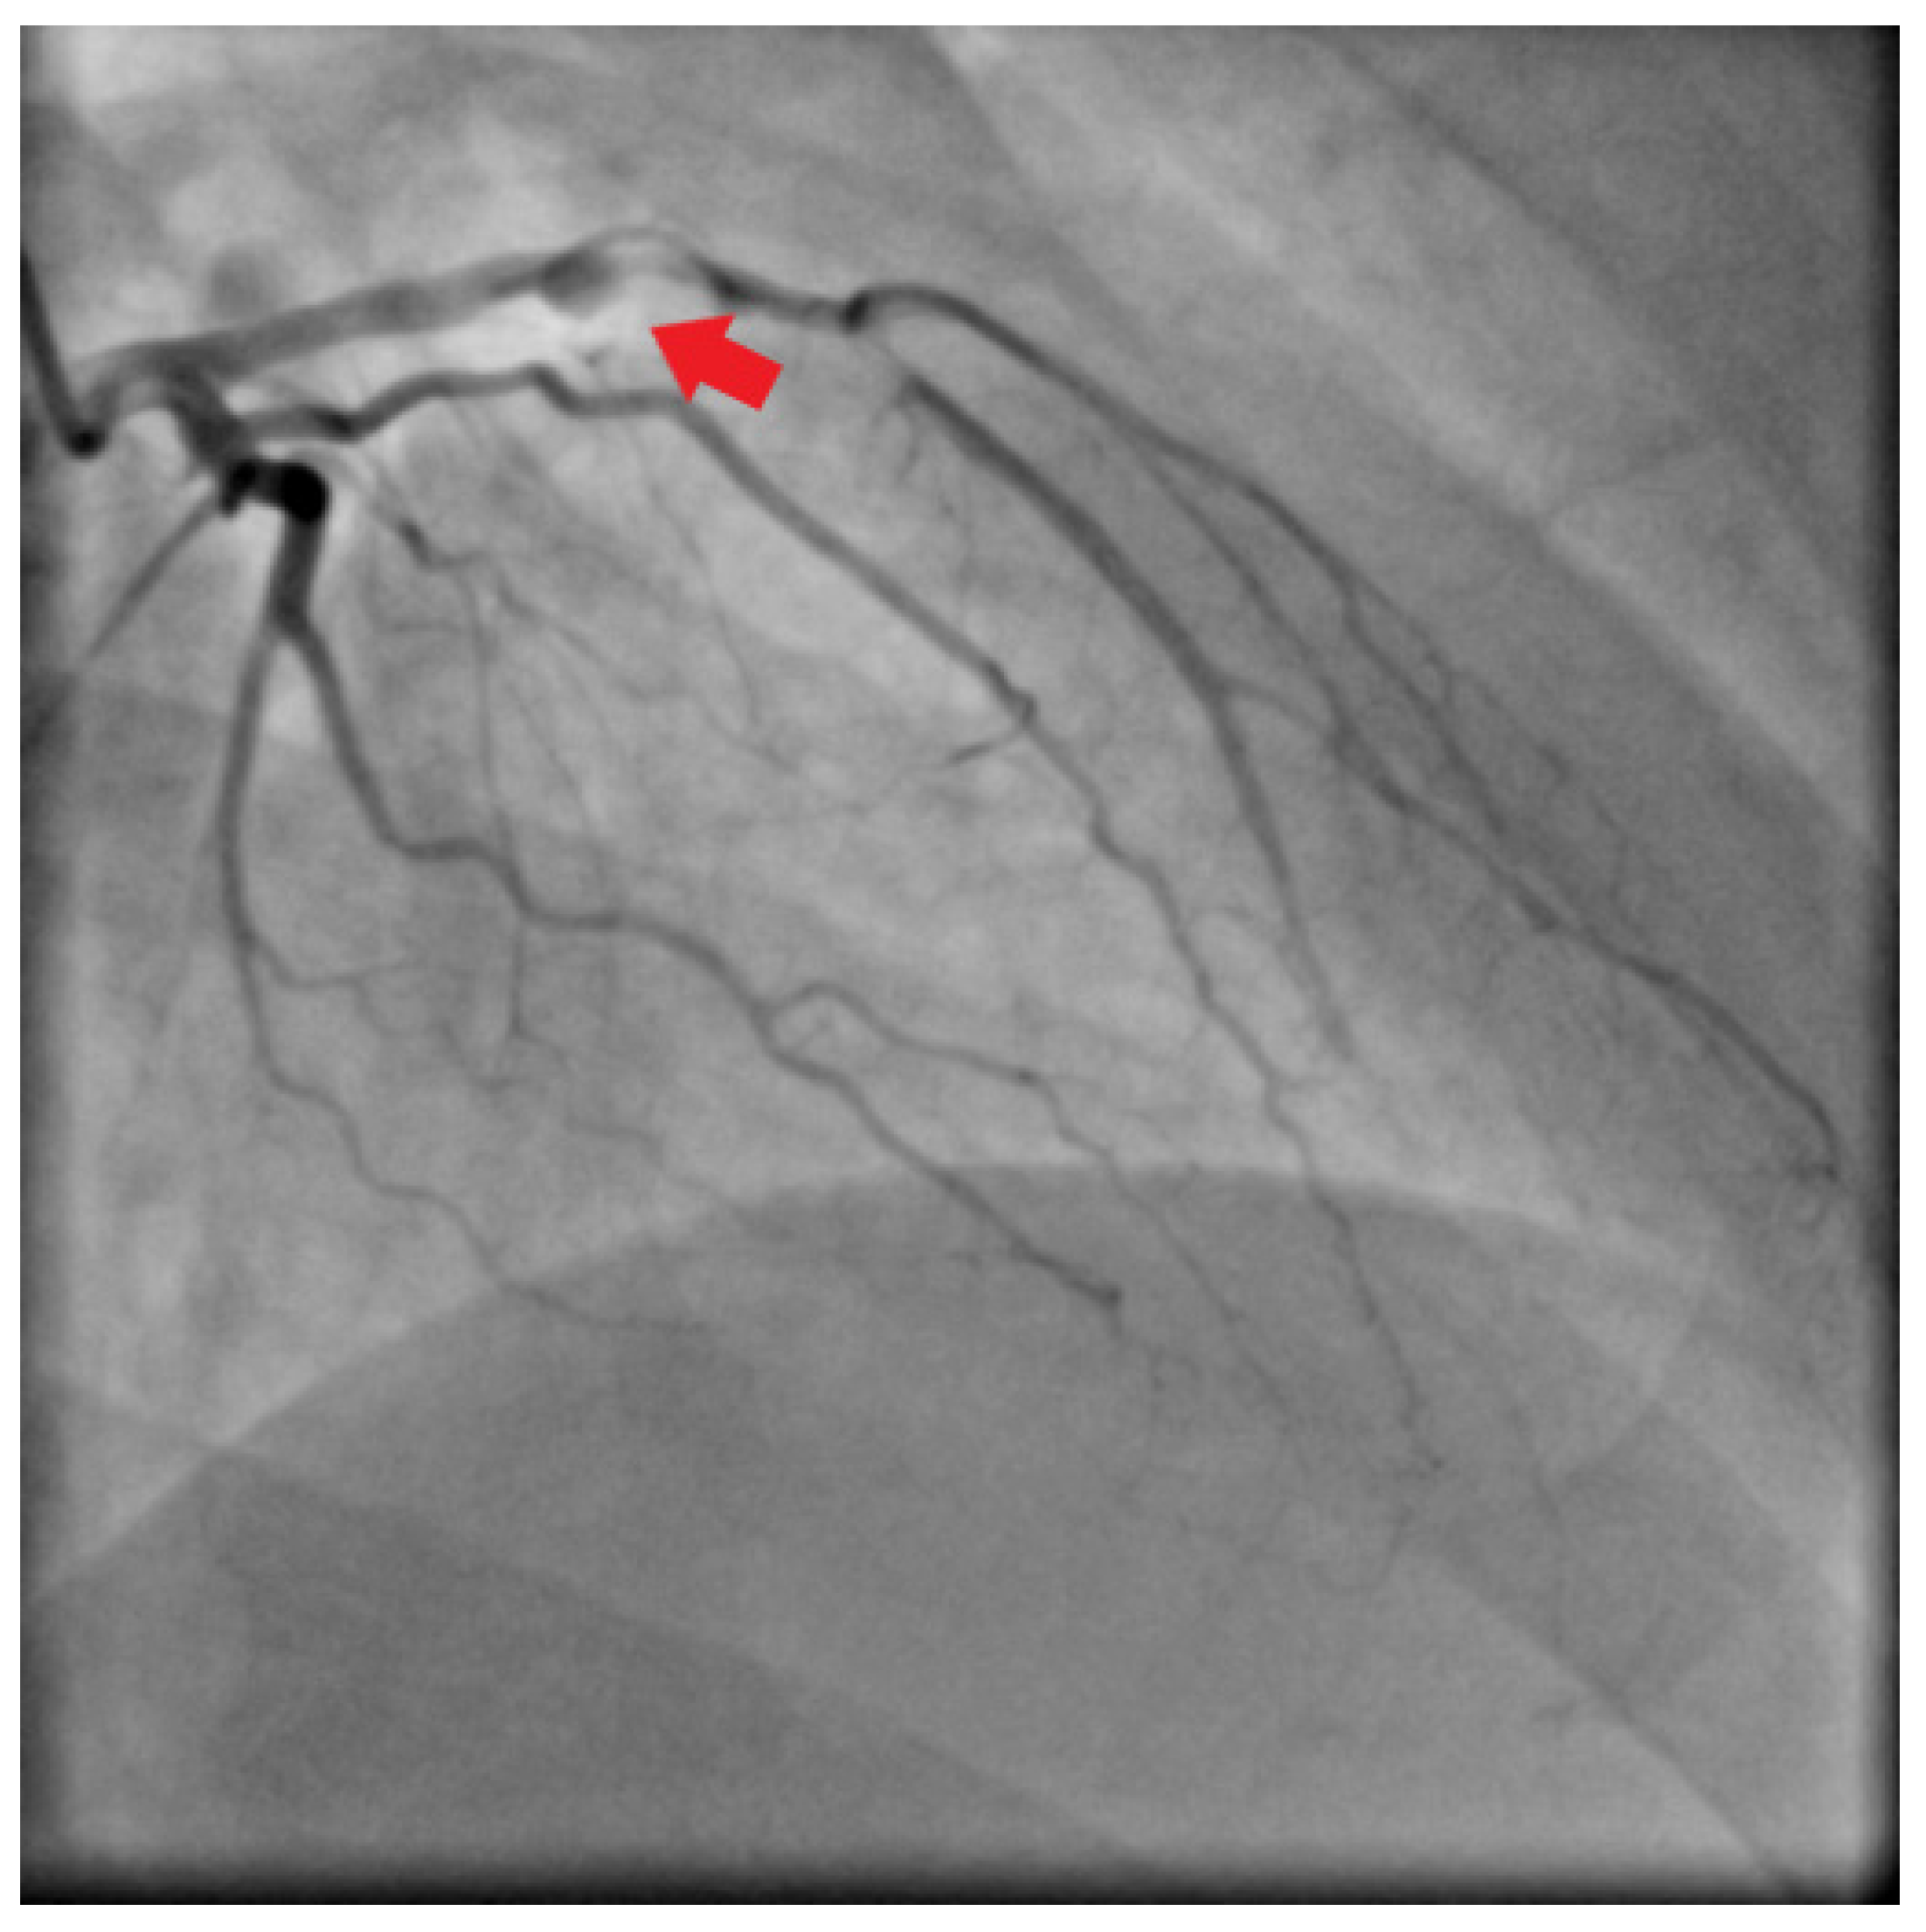

2. Case Report